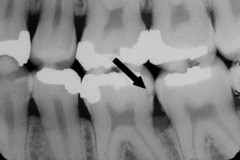

vertical bone loss

Front

Back